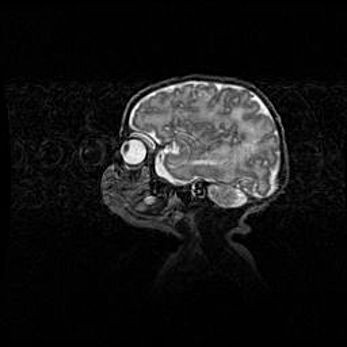

Мальформация Денди-Уокера. Киста задней черепной ямки.

Агенезия мозолистого тела.

Возраст: 2,5 месяца

Вес: 2420 г

Пол: женский

Окружность головы: 37 см

Срок гестации: 32 недели

Мальформация Денди—Уокера — редкий вид патологии ЦНС, представляющий собой врожденный порок развития каудального отдела ствола и червя мозжечка, ведущий к неполному раскрытию срединной (Мажанди) и латеральных (Лушка) апертур IV желудочка мозга. Для этогно синдрома характерна триада симптомов: гипотрофия червя мозжечка и/или полушарий мозжечка, кисты задней черепной ямки, гидроцефалия различной степени. В 70% случаев порок сочетается и с другими аномалиями головного мозга, в частности с агенезией мозолистого тела.